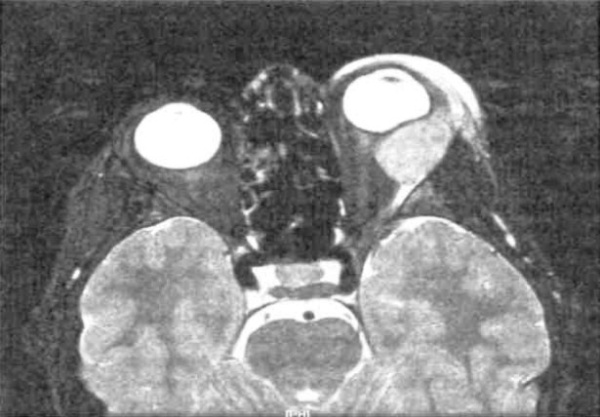

- МРТ орбиты. На МРТ-снимках определяются объемные новообразования неправильной формы, которые изоинтенсивны по отношению к мышцам орбиты и гиперинтенсивны относительно жировой клетчатки. Изредка визуализируется утолщение и инфильтрация глазных мышц.